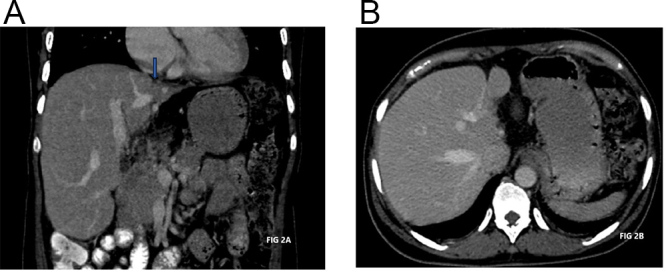

Case presentation: A 39-year-old woman presented with right lower abdominal pain, fever, and vomiting. Initially diagnosed with an appendicular lump, she was managed conservatively and discharged after symptomatic improvement. Upon recurrence of symptoms, imaging revealed an ovarian dermoid cyst with torsion. Exploratory laparotomy identified a gangrenous ovary with a twisted cyst and adherent appendix. Histopathology confirmed acute appendicitis and a benign dermoid cyst.

Discussion: Adnexal torsion occurs when the ovary and fallopian tube twist around their ligaments, often caused by ovarian cysts like dermoid cysts. These cysts are common in young women and can lead to acute abdominal pain, requiring urgent surgery to prevent ovarian damage. Diagnosis is challenging, as symptoms mimic other conditions like appendicitis. Imaging such as ultrasonography or computed tomography is used, and treatment involves surgical untwisting or removal of affected tissues. Torsion sometimes affects nearby organs, like an appendix.